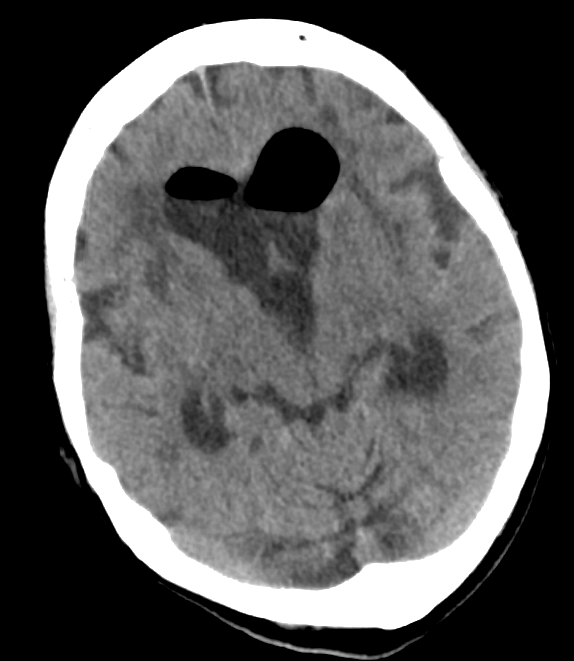

How to identify pneumocephalus on a head CT.

Air occasionally enters the cranium and fills the ventricles – usually after a neurosurgical procedure, severe head trauma, or ventriculostomy placement. Air inside the skull is called pneumocephalus.

Although high flow oxygen can be used to help speed up the absorption of free air, but post-surgical pneumocephalus tends to be asymptomatic and resolves spontaneously. Take a look at the axial head CT below – do you see the free air? Scroll to the bottom for an annotated image.

Air has an extremely low density on head CT, and should appear black, no matter how you window the head CT. One of the easiest ways to verify that something dark is air, rather than another hypodense material such as fat, is to look at the CT using the bone window, a setting which shows detail in highly dense structures. Air should remain dark even when viewing the head CT in this way – see the example below.